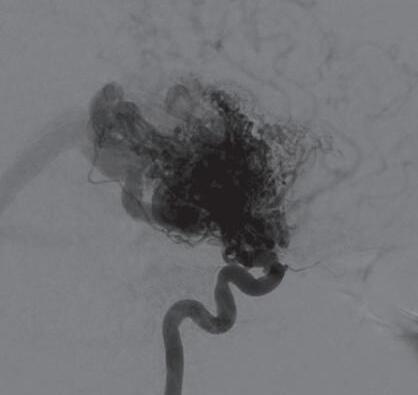

Fig. 1-16. RNM encéfalo T1 com contraste: (a) Coronal e (b) axial demonstrando MAV grau 4 frontoparietal esquerda. (c,d) Arteriografia cerebral AP mostrando a irrigação pelos ramos da cerebral anterior e média esquerda, além da cerebral anterior direita, com drenagem superficial para o seio sagital superior. Seta azul apontando para o nidus da MAV.

Fig. 1-17. RNM encéfalo T1 com contraste (a) axial e (b) T2 sagital demonstrando MAV grau 5 profunda temporoinsular esquerda com extensão nos núcleos da base. (c,d) Arteriografia cerebral,demonstrando a drenagem venosa profunda para veia cerebral interna (seta azul) com sinais de hipertensão.